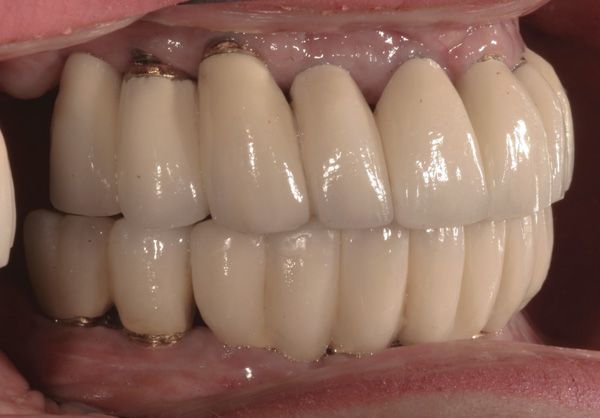

Background: The patient in this case presented with a failing dentition due to generalized severe periodontal disease with secondary endodontic lesions. She adamantly refused to wear removable transitional prostheses. Full maxillary and mandibular extractions were performed in the first phase of treatment. Not all implants could be placed in this initial phase due to the need for healing of certain grafted sites. The implants placed in this first phase were loaded with conical abutments and, in some cases, their angulated counterparts (Figure 16 and Figure 17). These stock titanium abutments were selected to avoid the need, as in Case 3, to change or remill the more costly custom abutments. They also have the advantage of making it unnecessary to use temporary cement near and around surgical sites, as they use occlusal screws only for retention.

Results: Stock titanium abutments were used until all tissue healing was achieved and the secondary implants had healed. Figure 18 shows the maxillary and mandibular custom abutments inserted. Figure 19 shows a close-up of the patient’s right side quadrants, depicting the final case 15 months after initial treatment began. Recession can be seen around units corresponding to tooth Nos. 5 and 6. In this case, the authors attempted to minimize recession susceptibility by employing stock temporary screw-retained abutments during healing phases throughout the initial stages of the treatment plan. Despite these efforts, recession still occurred in certain areas where the implants were labially placed. Since the photographs shown in this case were taken, an unsuccessful attempt was made by the patient’s surgeon to graft soft tissue around these sites with recession.

Figure 16 First-phase implants loaded with conical abutments and, in some cases, their angulated counterparts.

Figure 16

Figure 17 First-phase implants loaded with conical abutments and, in some cases, their angulated counterparts.

Figure 17

Figure 18 Custom abutments inserted.

Figure 18

Figure 19 Final result 15 months after initial treatment began, showing patient’s right side quadrants.

Figure 19